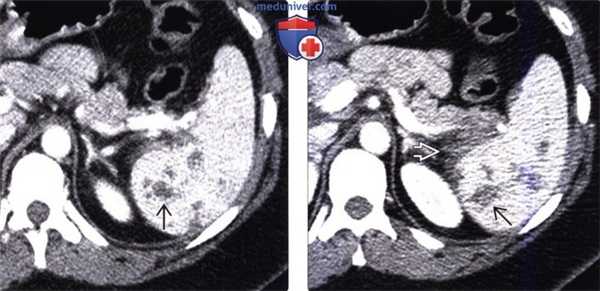

(Слева) На аксиальной КТ с контрастным усилением, выполненной пациенту после спленэктомии по поводу травмы, селезенка не визуализируется; определяются небольшие узелки, накапливающие контраст, в верхних отделах слева. Изменения, обусловленные спленозом, часто обнаруживаются в непосредственной близости к ложу селезенки.

(Справа) На аксиальной КТ с контрастным усилением у этого же пациента определяются еще несколько участков ткани селезенки, располагающиеся на серозной поверхности нисходящей ободочной кишки и у заднего края правой доли печени. Ткань селезенки при спленозе обычно располагается в брюшной полости; экстраперитонеальный спленоз встречается намного реже. (Слева) На аксиальной КТ с контрастным усилением у пациента с давней травмой живота в анамнезе определяются многочисленные мягкотканные узелки (спленоз) на поверхности органов, покрытых брюшиной, которые можно ошибочно принять за канцероматоз.

(Справа) На аксиальной КТ с контрастным усилением в области левого кардио-диафрагмального угла визуализируется мягкотканный узелок, накапливающий контраст. В анамнезе у пациента имеются данные о давней тупой травме живота с травматическим разрывом диафрагмы, что является наиболее распространенной причиной внутригрудного спленоза, намного реже встречающегося по сравнению со спленозом внутрибрюшной или тазовой локализации.